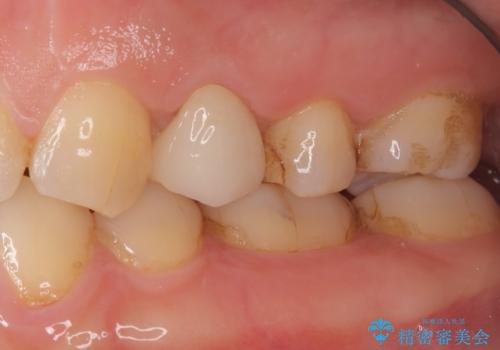

- 他院で昔に根管治療を行ったが、歯肉を押したときの痛みと普段の違和感が残ったままであることを主訴に来院されました。

以前治療した病院では、再根管治療を行わずに歯根端切除のみでの対応を進められたが、治療方針に納得できず当院を受診されました。

治療介入における意思決定が重要となるケースでしたが、患者と相談して①再根管治療→②外科的歯内療法という流れで治療を行いました。

再根管治療を優先した理由としては、破折診断と、当時の治療においてラバーダムや顕微鏡を使用してないとの話があったためです。

結果、根管内にはイスムスにデブリが多く見られたものの破折線は確認できませんでした。再根管治療後、症状の経過を3ヶ月ほど確認しましたが打診、違和感が消失しておらず、外科的歯内療法を行うこととなりました。